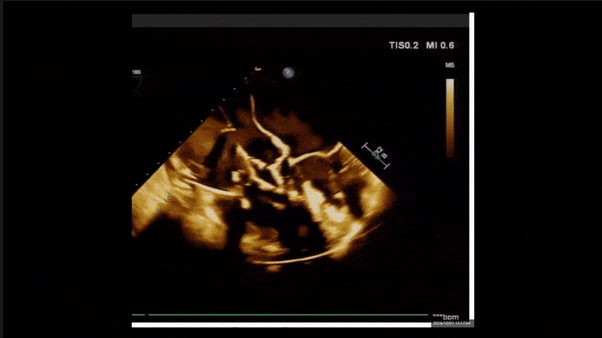

術后即刻返流三維

術后三維超聲

術后即刻經食道超聲可見,三尖瓣假體瓣膜位置合適,牛心包瓣葉運動狀態良好,開閉正常,瓣周及瓣葉對合緣處未見明顯返流,心電圖及心包狀態較術前無明顯變化。

術前術后返流情況對比